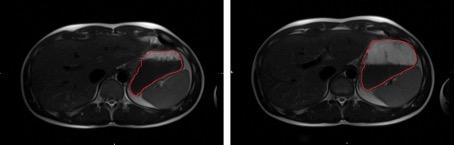

Figure 2.

The same subject with either the small (left) or large volume of water (right) in the stomach (delineated in red).